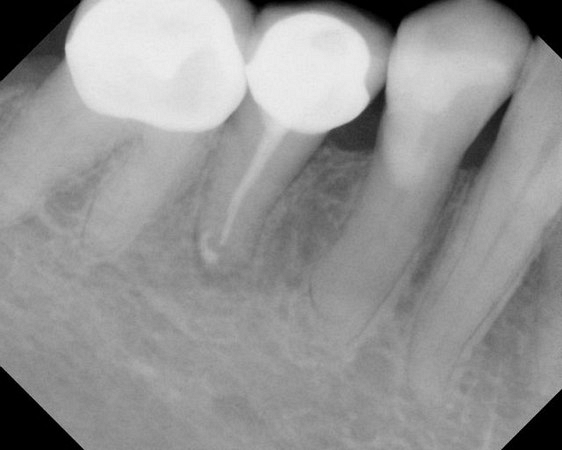

See xrays of before and after a root canal is completed below